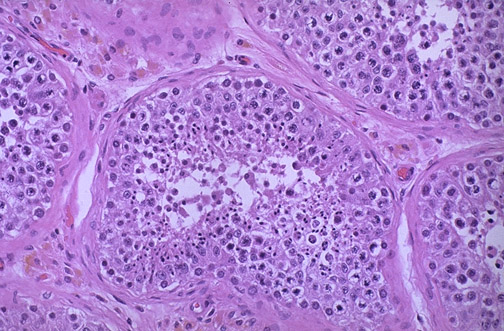

Pink Leyding cells are seen here in the interstitium. Note the pale golden brown pigment within the cytoplasm of these cells as well. There is active spermatogenesis in the seminiferous tubules.